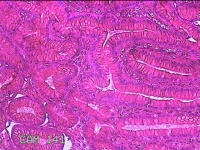

胃窦粘膜

性别

女

年龄

52岁

临床诊断

胃食管反流?;慢性胃炎

一般病史

吞咽困难2年余。

标本名称

大体所见

灰白粉红色组织小米大一团。

图2

有可能是慢性炎,片子这个效果,猜起来比较困难,